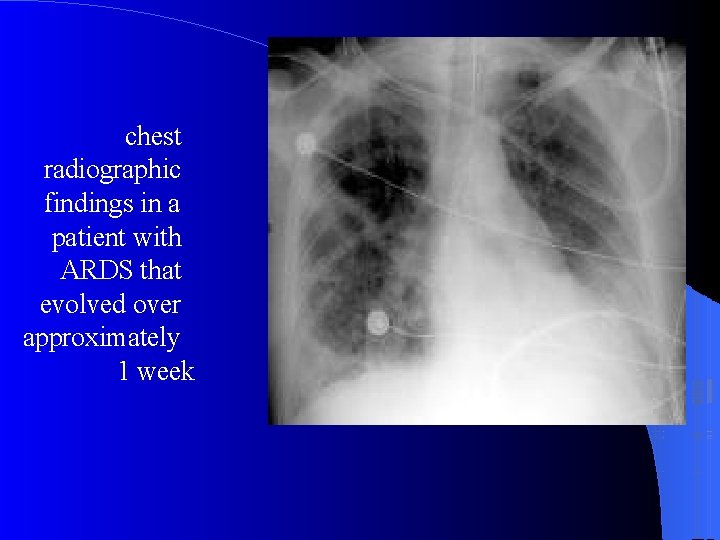

CXR Chest radiographic findings are non-specific and resemble those of typical pulmonary edema or pulmonary hemorrhage. There are diffuse bilateral coalescent opacities (the only radiological criterion defined by the Consensus Conference). The time course of ARDS may help in differentiating it from typical pulmonary edema. Chest x-ray features usually develop 12 -24 hours after initial lung insult as a result of proteinaceous interstitial edema. Within one week, alveolar pulmonary edema (hyaline membrane) occurs due to type 1 pneumocyte damage. In contrast to cardiogenic pulmonary edema, which clears in response to diuretic therapy, ARDS persists for days to weeks.

The patient had been in respiratory failure for 1 week with the diagnosis of ARDS. .

chest radiographic findings in a patient with ARDS that evolved over approximately 1 week

Late stage of ARDS showing bilateral and diffuse alveolar and reticular opacification